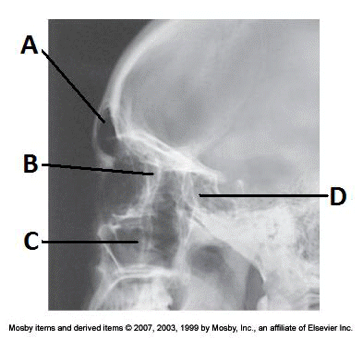

4. Examine the image of the paranasal sinuses below. The letter D labels the:

a. maxillary sinuses

b. ethmoid sinuses

c. sphenoid sinuses

d. frontal sinuses

__ 7. Examine the image of the paranasal sinuses below. The letter B labels the:

a. ethmoid sinuses

b. sphenoid sinuses

c. maxillary sinuses